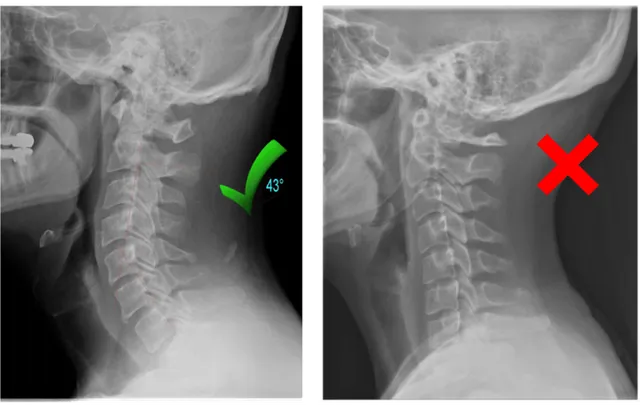

2. Your Neck Has Lost Its Natural Curve

Years of looking down at phones, working at desks, and poor sleeping posture can flatten the natural curve of your neck.

This leads to collapsed vertebrae, pinched nerves, and chronic pain that no massage or pillow can fix.

Restoring the natural curve in your neck